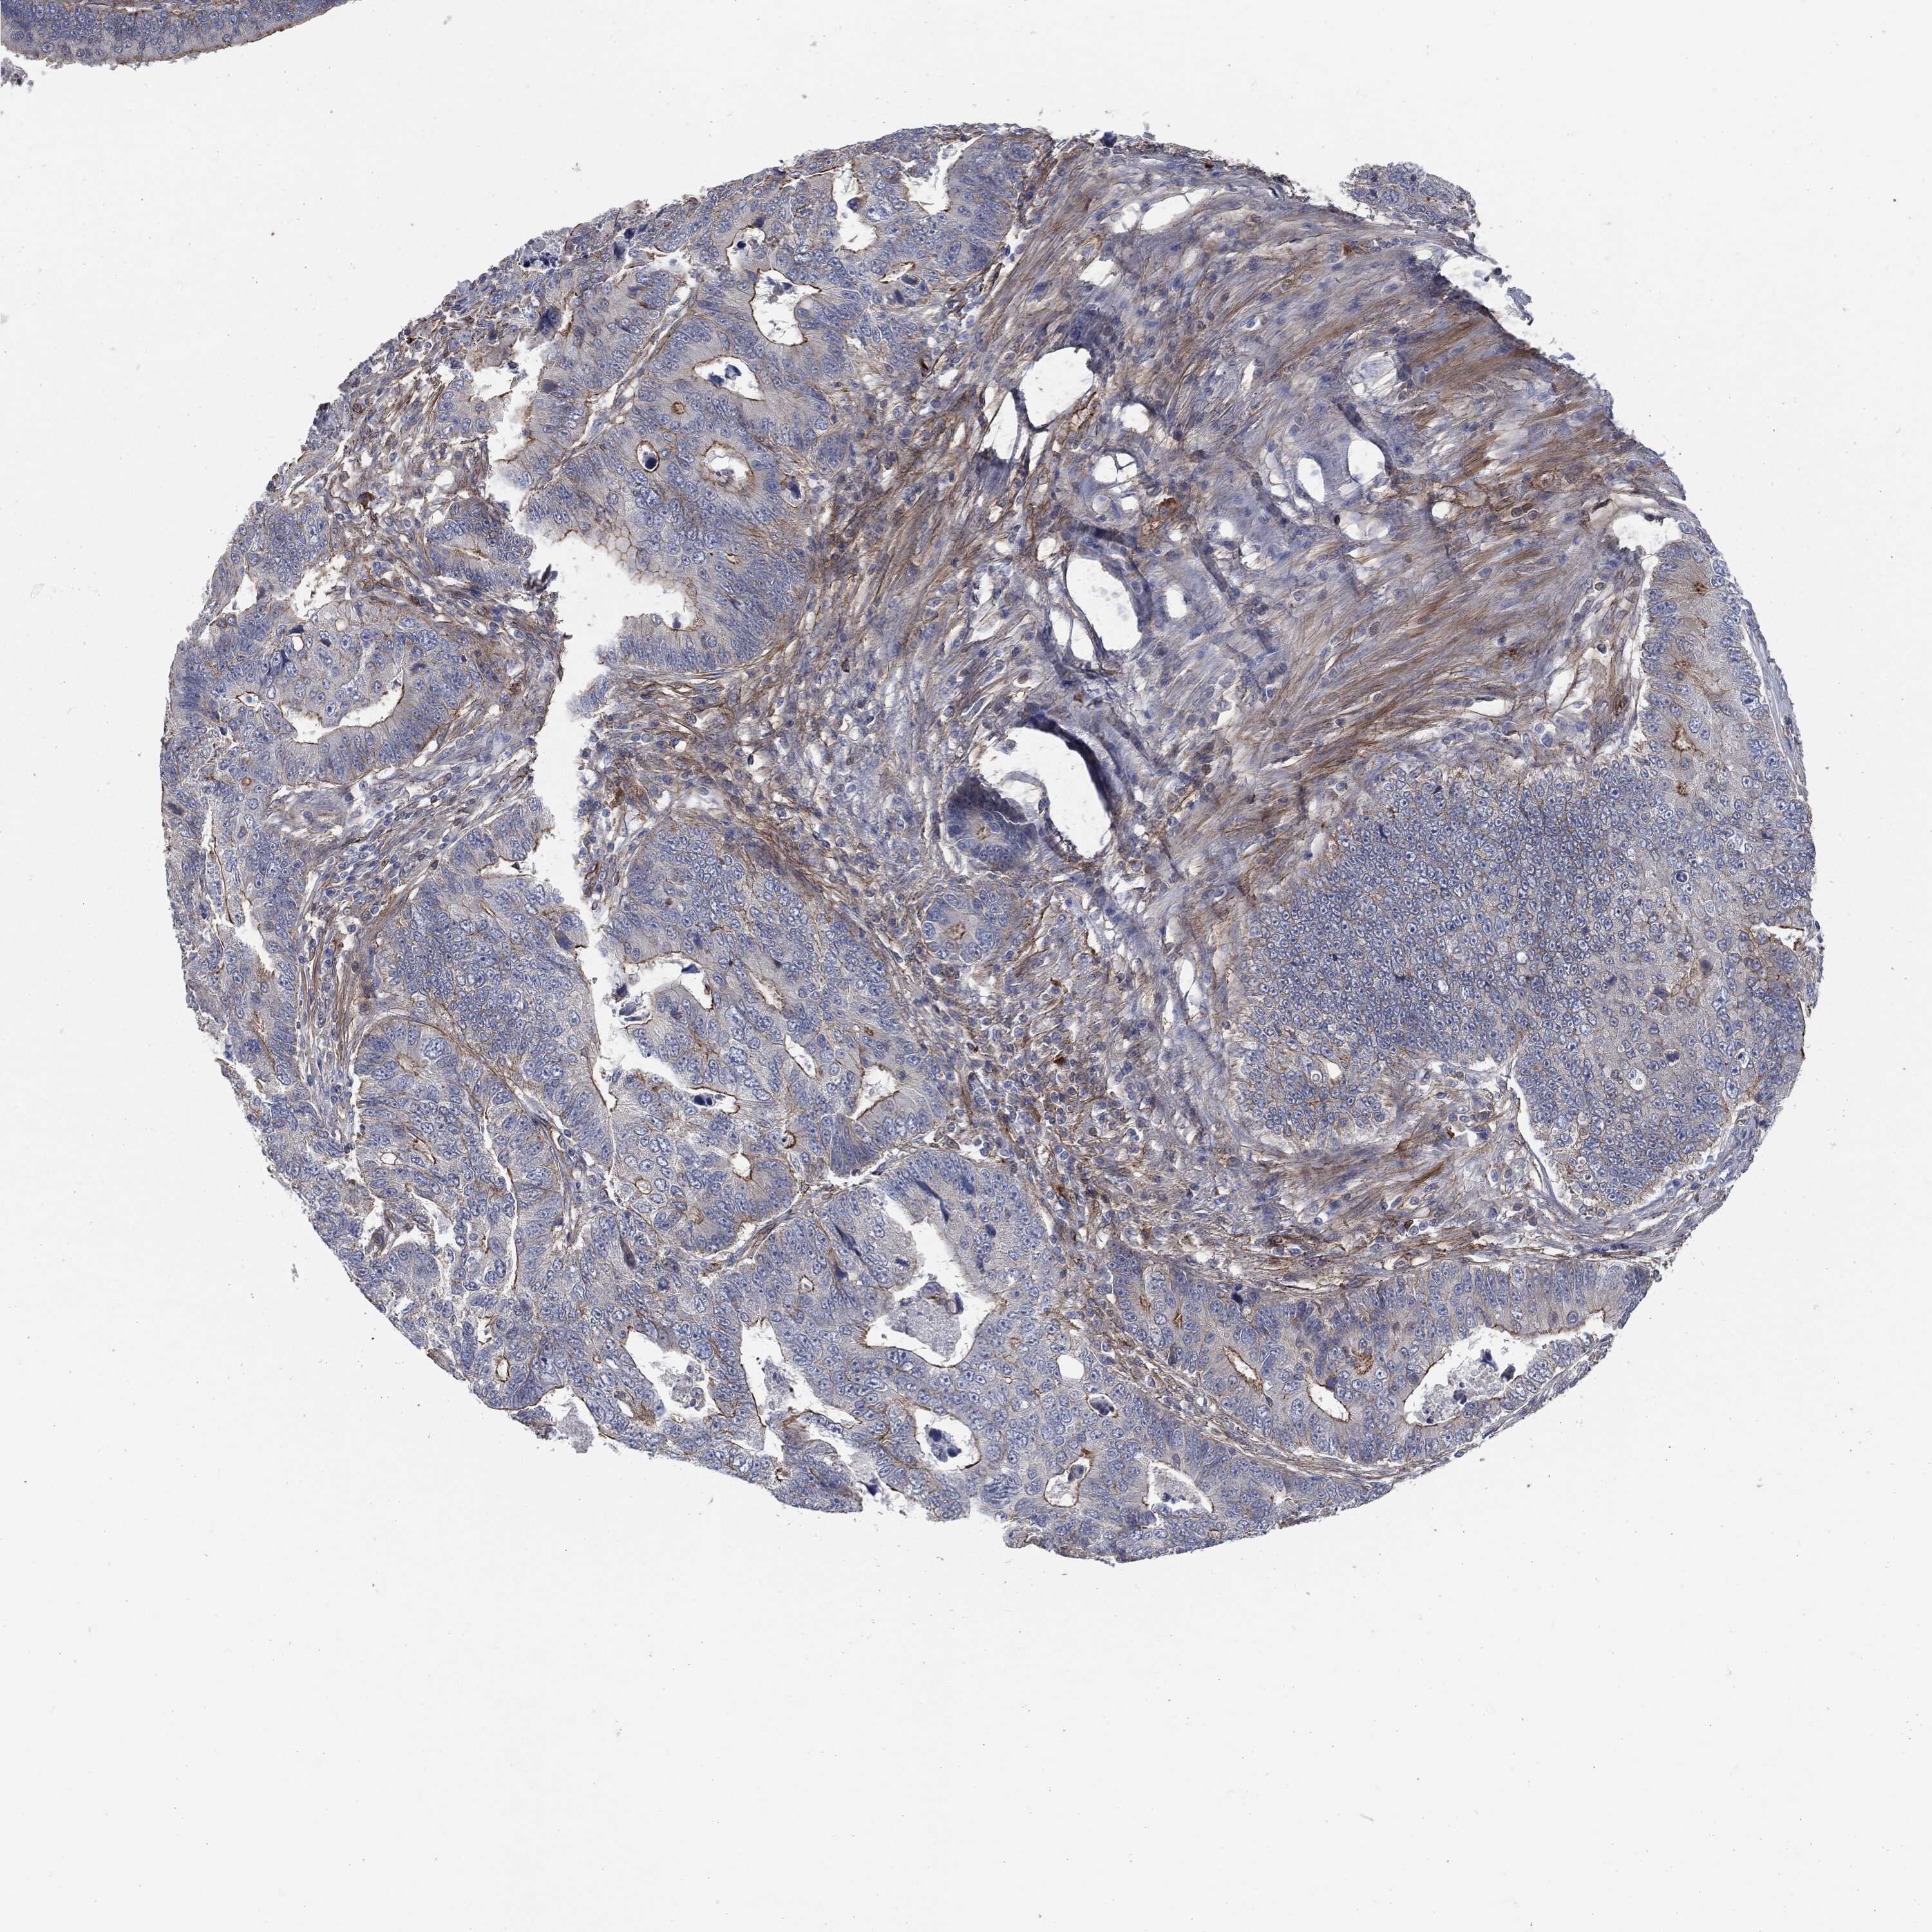

RECTUM ADENOCARCINOMA (TCGA) - Interactive survival scatter ploti

The Survival Scatter plot shows the clinical status (i.e. dead or alive) for all individuals in the patient cohort, based on the same data that underlies the corresponding Kaplan-Meier plots. Patients that are alive at last time for follow-up are shown in blue and patients who have died during the study are shown in red.

The x-axis shows the expression levels (FPKM) of the investigated gene in the tumor tissue at the time of diagnosis. The y-axis shows the follow-up time after diagnosis (years). Both axes are complimented with kernel density curves demonstrating the data density over the axes. The top density plot shows the expression levels (FPKM) distribution among dead (red) and alive patients (blue). The right density plot shows the data density of the survived years of dead patients with high and low expression levels respectively, stratified using the cutoff indicated by the vertical dashed line through the Survival Scatter plot. This cutoff is automatically defined based on the FPKM cutoff that minimizes the p-score. The cutoff can be changed by dragging the vertical line or by entering a cutoff value in the square labeled "Current cut-off".

Under the Survival Scatter plot the p-score landscape (black curve; left axis) is shown together with dead median separation (red curve; right axis). Dead median separation is the difference in median mRNA expression between patients who have died with high and low expression, respectively. It is calculated as follows: median FPKM expression of dead patients with high expression - median FPKM expression of dead patients with low expression. This is intended to aid the user in visually exploring custom cutoffs and the associated p-scores and dead median separation.

Individual patient data is displayed and can be filtered by clicking on one or more of the category buttons on the top of the page. Categories describing expression level and patient information include: high, low, alive, dead, female, male and tumor stages. The scale of the x-axis can be toggled between linear and log-scale by clicking on the "x log" button. Mouse-over function shows TCGA ID, patient information and mRNA expression (FPKM) for each patient.

& Survival analysisi

Kaplan-Meier plots summarize results from analysis of correlation between mRNA expression level and patient survival. Patients were divided based on level of expression into one of the two groups "low" (under cut off) or "high" (over cut off). X-axis shows time for survival (years) and y-axis shows the probability of survival, where 1.0 corresponds to 100 percent.

SVIL is not prognostic in Rectum Adenocarcinoma (TCGA)

Best expression cut offi

Based on the FPKM value of each gene, patients were classified into two groups and association between prognosis (survival) and gene expression (FPKM) was examined. The best expression cut-off refers the FPKM value that yields maximal difference with regard to survival between the two groups at the lowest log-rank P-value. Best expression cut-off was selected based on survival analysis .

When clicking on this number, the vertical dashed line indicating cut-off, the interactive survival plot, and the Kaplan-Meier curve will be adjusted to show results based on the best expression cut-off.

: 25.04

P scorei

Log-rank P value for Kaplan-Meier plot showing results from analysis of correlation between mRNA expression level and patient survival.

N/A

TCGA RNA samplesi

RNA-seq data is reported as average FPKM (number Fragments Per Kilobase of exon per Million reads), generated by the The Cancer Genome Atlas (TCGA) .

Normal distribution across the dataset is visualized with box plots, shown as median and 25th and 75th percentiles. Points are displayed as outliers if they are above or below 1.5 times the interquartile range. FPKM values of the individual samples are presented next to the box plot.

Average pTPM 19.9

Number of samples 88